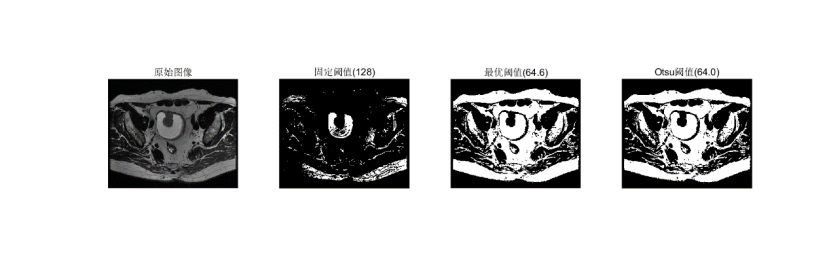

它利用图像中要提取的目标与背景在灰度上的差异,通过设置阈值来把像素分成若干类,从而实现目标与背景的分离。阈值分割有以下几种方法:(1)固定阈值分割(2)迭代阈值分割(3)大津法OTSU(4)自适应阈值分割

1.1固定阈值分割

将灰度值大于某一阈值的像素点设置为255,而小于等于该阈值的点设置为0。函数说明:函数threshold()可以将灰度图像转换为二值图像,图像完全由像素0和255构成呈现出只有黑白两色的视觉效果。经过二值化处理后的图像(Fix Iamge),仅包含黑白像素,用于分离目标与背景。